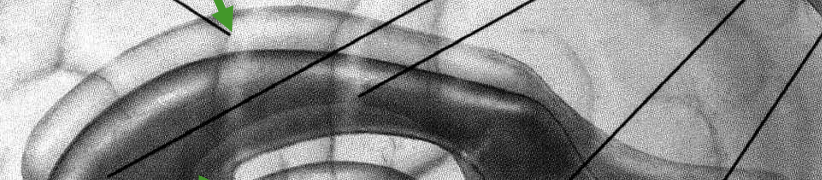

ICP

MCP

SCP

cerebellar peduncles:

inferior cerebellar peduncles

connect the cerebellum to the medulla

middle cerebellar peduncles

connect the cerebellum to the pons; THE ONLY ONE YOU CAN SEE

superior cerebellar peduncles

connect the cerebellum to the midbrain